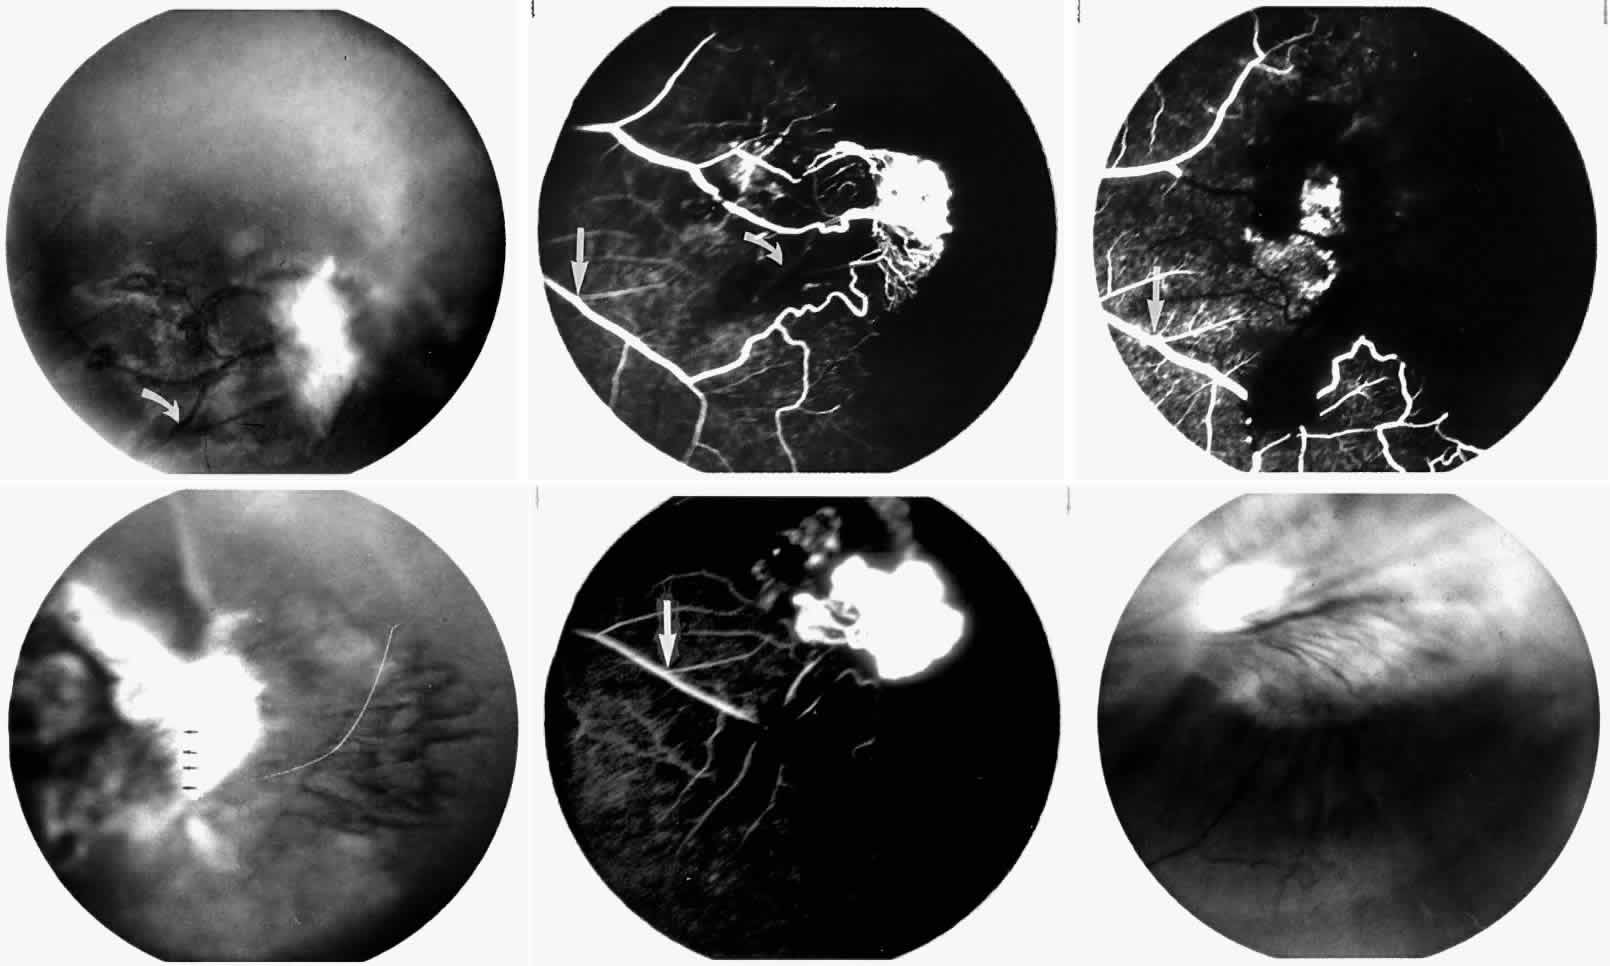

Occlusions of the central retinal artery and major arteriolar branches are probably most frequent in young patients with homozygous sickle cell anemia; however, they may also occur with other sickling genotypes (Fig. 7).39,83,84 They may cause permanent or transient visual loss and can occur simultaneously in both eyes.85–87 Arterial occlusion has also been reported to occur as a complication of retrobulbar anesthesia and following compression of the eye during photocoagulation (Fig. 8).88

Fig. 7. Transient perimacular arteriolar occlusions in a 32-year-old patient with SC disease, who presented with decreased vision in the right eye (20/40) after being tackled while playing football. A. Photograph of right macula showing a white, edematous retina and a cherry red spot due to multiple arteriolar occlusions. B. Fluorescein angiogram shows multiple avascular areas, particularly at the temporal raphe (arrowheads), and an irregular perifoveal capillary network (open arrows).

Fig. 8. A 27-year-old woman with homozygous sickle cell anemia and stage III sickle cell retinopathy. A. Three days after scatter photocoagulation to the right eye, a photograph of the right eye shows retinal arteriolar occlusions causing a white, edematous macula, a cherry red spot, and a cotton-wool spot superior to the macula. B. Fluorescein angiogram clearly shows the occluded arteriole superiorly, but no occlusion in the perifoveal or temporal macula. C. However, a fluorescein angiogram taken 1 year later demonstrates an irregular perifoveal capillary network with areas of capillary nonperfusion (arrows). D. Of interest, the left eye simultaneously developed an area of capillary nonperfusion, demonstrated by a cotton-wool spot nasal to the fovea. E. Two years later, there is resolution of the cotton-wool spot in the left eye, but a retinal depression sign remains, as demonstrated by an abnormal light reflex in the area nasal to the fovea (arrows).

Occlusions of the fine vasculature of the macular and perimacular area have been reported in 10% to 40% of patients with sickle cell disease.18,83,91–99 In the acute phase, the occluded vessel will have a dark red appearance and may appear as a dark line on fluorescein angiography (Fig. 9). Nerve fiber layer infarcts (cotton-wool spots) are seen (see Fig. 8D and E;Fig. 10).100

Fig. 9. A 27-year-old man with homozygous sickle cell anemia. A. Fluorescein angiogram of the right eye shows multiple arteriolar occlusions temporal to the fovea (arrows). B. Same area 6 months later shows more extensive occlusions. The black arrowheads (A and B) identify corresponding arteriolar bifurcation.

Fig. 10. A 33-year-old woman with SC disease and stage III sickle cell retinopathy. A. Photograph of the right eye shows a cotton-wool spot with a dark segment identifying the occluded vessel (arrow). B. Fluorescein angiogram demonstrates nonfilling of the occluded vessel (arrow). C. Eighteen months later, the occluded vessel is still visible (arrow). D. Fluorescein angiogram demonstrates that there is still nonfilling of the vessel (arrow).

Other macular and perimacular changes include microaneurysm-like dots, dark and enlarged segments of arterioles, hairpin-shaped venular loops, pathologic avascular zones, and widening and irregularities of the foveal avascular zone (Figs. 11 and 12). In the Jamaican cohort study evaluating children with homozygous sickle cell anemia and SC disease between the ages of 5.0 and 7.5 years of age, no pathologic avascular zones could be identified despite a high incidence of peripheral vascular closure.31 In evaluating patients with homozygous sickle cell anemia, no relationship between ISC counts and macular abnormalities or visual acuity could be found.101 Using fluorescein angiography, investigators have found the foveal avascular zone to be significantly larger in eyes with clinical evidence of sickle cell maculopathy as compared with normal eyes and eyes without clinical evidence of sickle cell maculopathy.102–104

Fig. 11. A. A 40-year-old woman with homozygous sickle cell anemia. A fluorescein angiogram demonstrates multiple microaneurysm-like dots with fluorescein leakage, hairpin loop (arrowhead), pathologic avascular zones (arrows), and a widened, irregular foveal avascular zone (FAZ). B. Fluorescein angiogram of a 30-year-old woman with homozygous sickle cell anemia demonstrates multiple microaneurysm-like dots and a widened, irregular FAZ.

Fig. 12. A. Fluorescein angiogram of the left eye of a 40-year-old man with homozygous sickle cell anemia, demonstrating an irregular foveal avascular zone (FAZ), hairpin loops, and loss of the temporal capillary network. B. Fluorescein angiogram of the right macula of a 38-year-old woman with homozygous sickle cell anemia, showing an abnormal FAZ, hairpin loop (arrowhead), and pathologic avascular zones (arrows).

Careful examination by fluorescein angiography, looking for areas of capillary dropout and other capillary abnormalities, is often necessary to identify the macular changes. These changes may be transient, and the macula may appear normal on subsequent fluorescein angiograms (Fig. 13). Although fluorescein angiography may or may not demonstrate reperfusion of a previously occluded capillary bed, a loss of the inner retinal layers results in an ophthalmoscopic focal concavity with an abnormal reflex (retinal depression sign) (see Fig. 8E).105,106 These changes are usually permanent. The retinal depression sign is not pathognomonic of sickle cell disease and may be seen with other arteriolar occlusive diseases, such as embolic retinopathy, vasculitis, and hypertension.

Fig. 13. A. A 32-year-old man with homozygous sickle cell anemia and proliferative sickle retinopathy. A fluorescein angiogram shows temporal occlusions and a pathologic avascular zone (PAZ) temporal to the foveal avascular zone. B. Seven years later, there is filling of the previously noted PAZ.